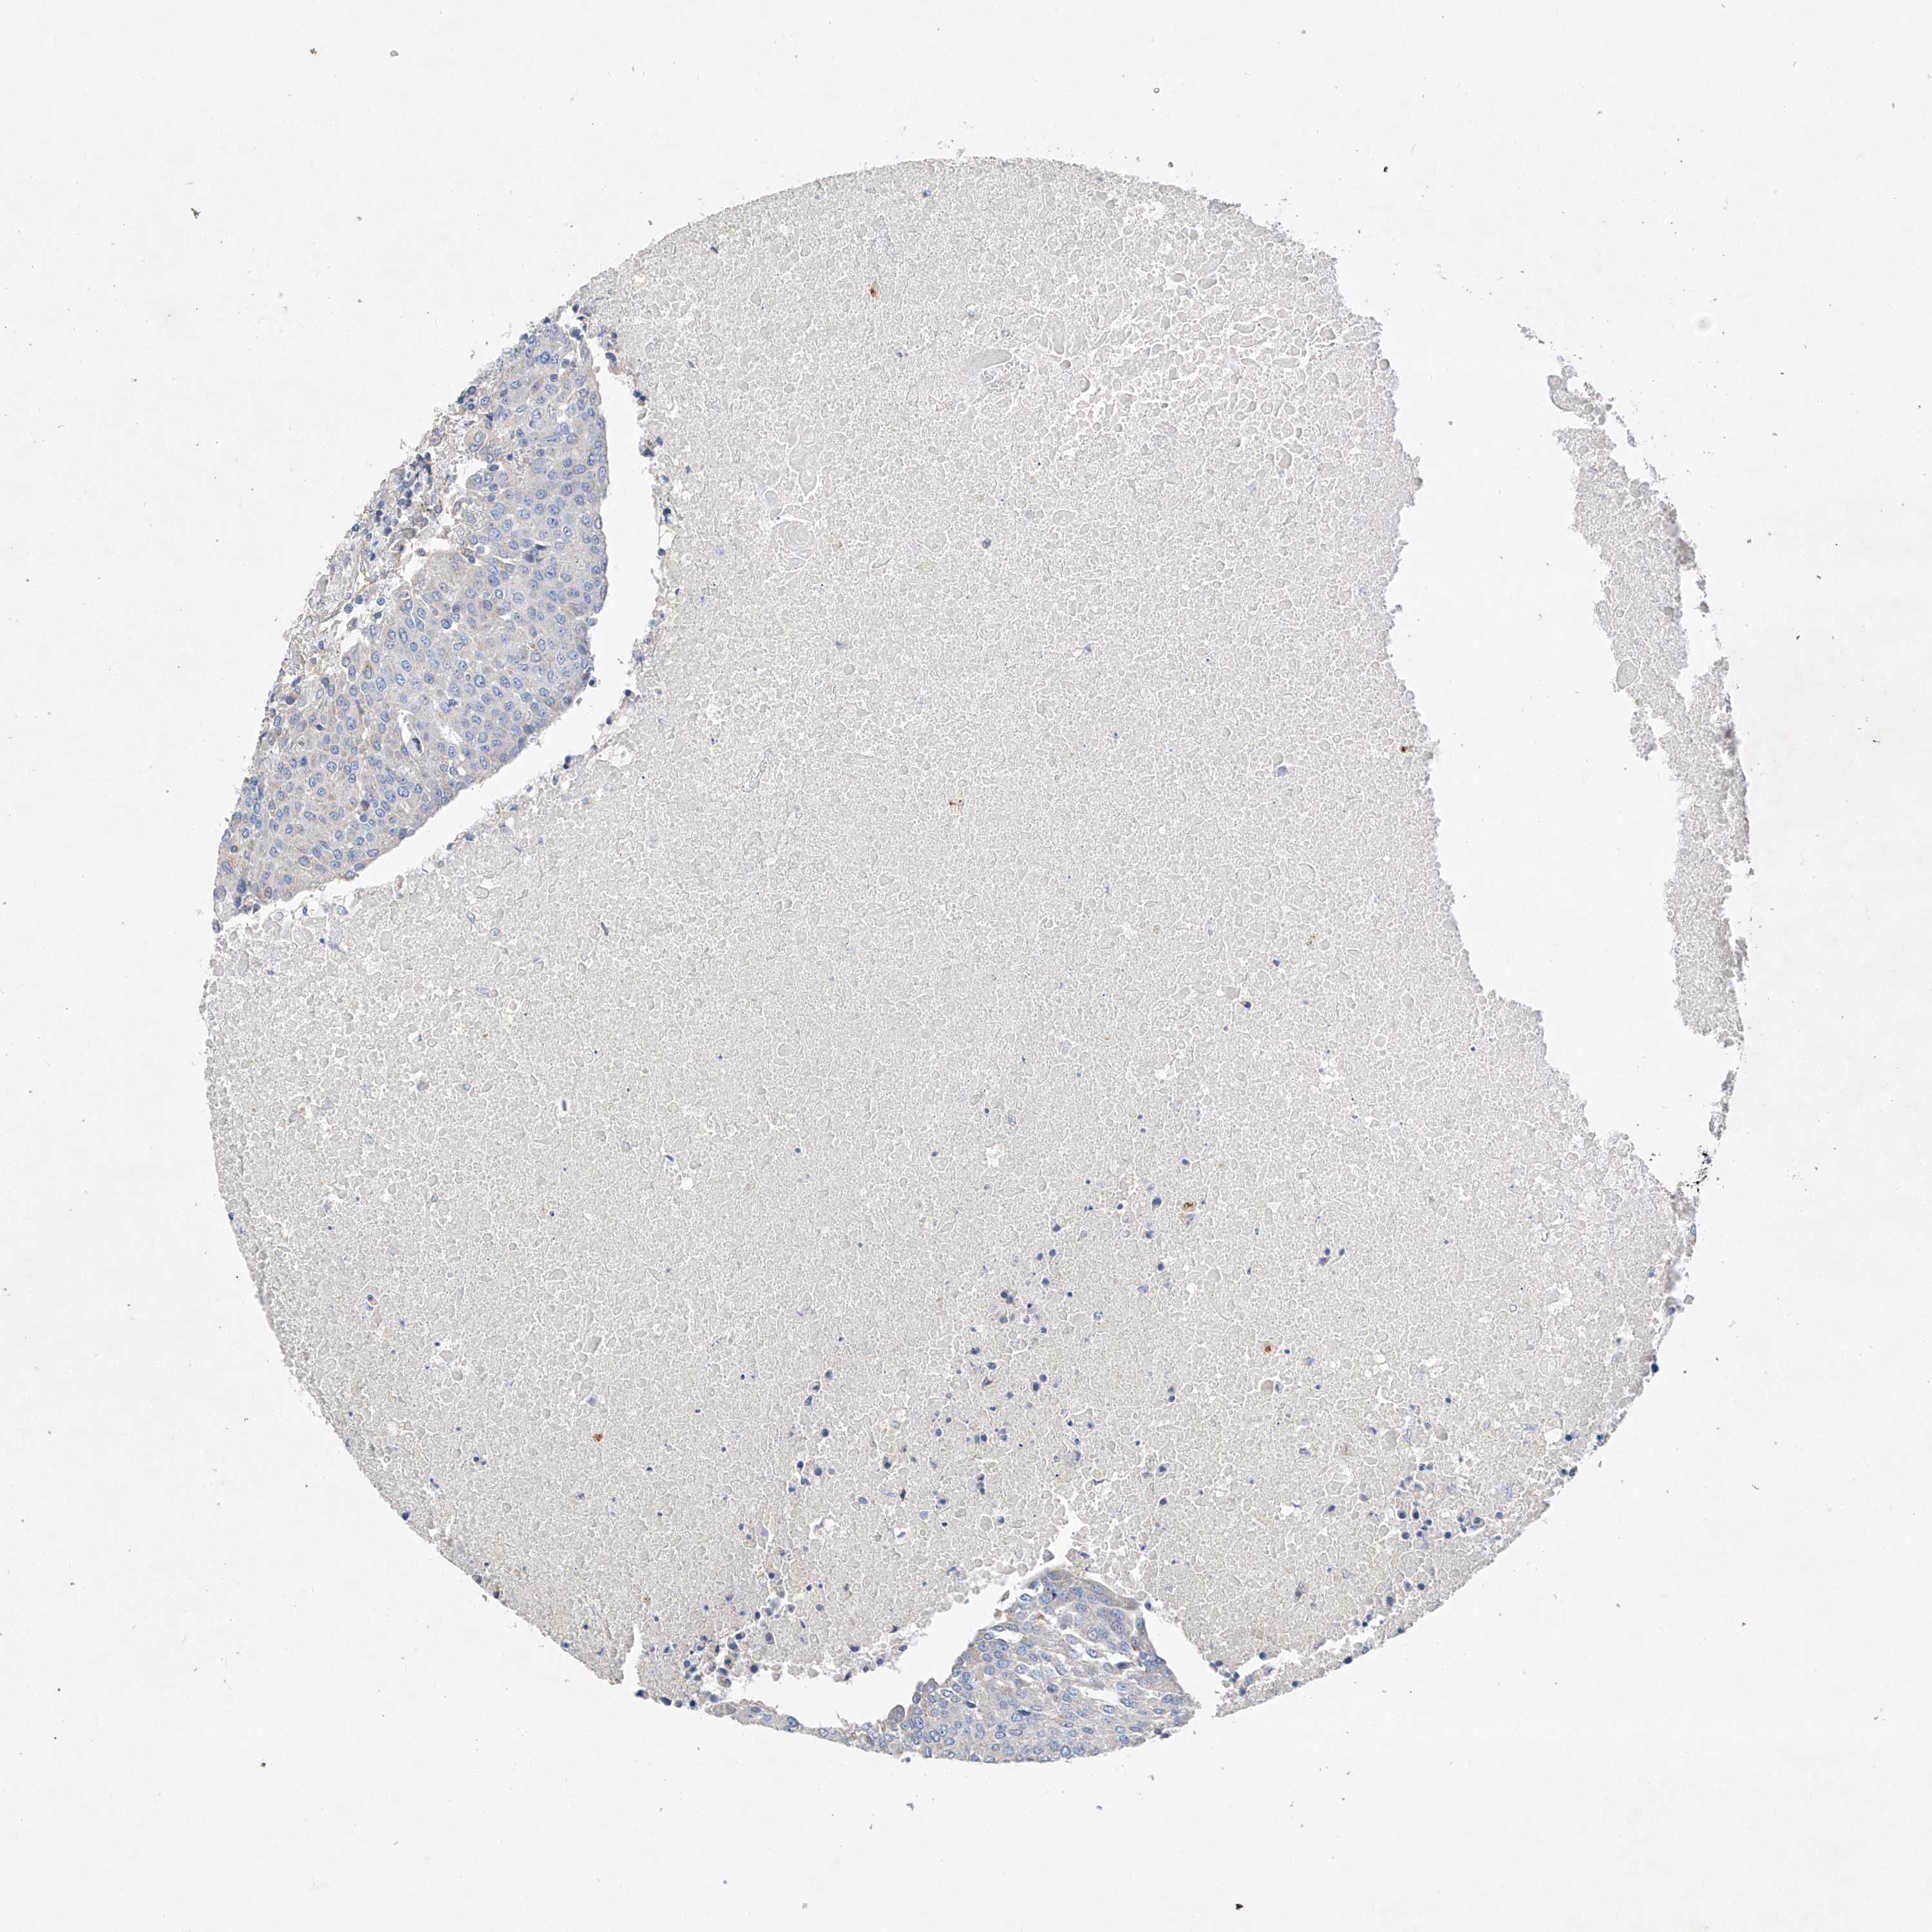

UROTHELIAL CANCER - Protein expressioni

A mouse-over function shows sample information and annotation data. Click on an image to view it in a full screen mode. Samples can be filtered based on level of antibody staining by selecting one or several of the following categories: high, medium, low and not detected. The assay and annotation is described here.

Note that samples used for immunohistochemistry by the Human Protein Atlas do not correspond to samples in the TCGA dataset.

Antibody stainingi

Antibody staining in the annotated cell types in the current human tissue is reported as not detected, low, medium, or high, based on conventional immunohistochemistry profiling in selected tissues. This score is based on the combination of the staining intensity and fraction of stained cells.

Each image is clickable and will lead to virtual microscopy that enables deeper exploration of all samples and also displays staining intensity scores, fraction scores and subcellular localization as well as patient and tissue information for each sample.

Antibody HPA029281

Antibody HPA029282

Urothelial carcinoma, Low grade